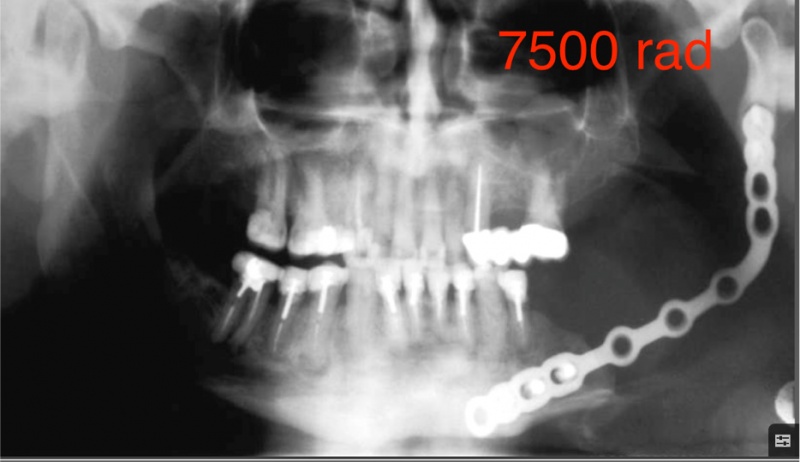

Is het mogelijk om implantaten te plaatsen bij patiënten die bestraald zijn geweest in de mondregio?

Absoluut! Dr. Defrancq zet zich graag in voor deze patiënten die bestraald zijn geweest voor een mondtumor.Het is een prachtige indicatie, omdat vele patiënten extreem pijnlijke en gevoelige tanden heeft na bestraling. Deze ingreep betekent ontzettend veel voor hen, niet alleen op functioneel vlak maar ook op vlak van comfort en zelfwaarde.

Een zorgvuldige werkwijze is noodzakelijk om de tanden zo atraumatisch mogelijk te verwijderen. Dr. Defrancq heeft dergelijke constructies bij een tiental patiënten uitgevoerd zonder noemenswaardige moeilijkheden en met immediate loading. Vaak wordt een uitvoering in porselein verkozen. Deze patiënten hebben immers vaak een heel droge mond hebben en onder deze omstandigheden voelt porselein veel comfortabeler aan dan hunsthars.